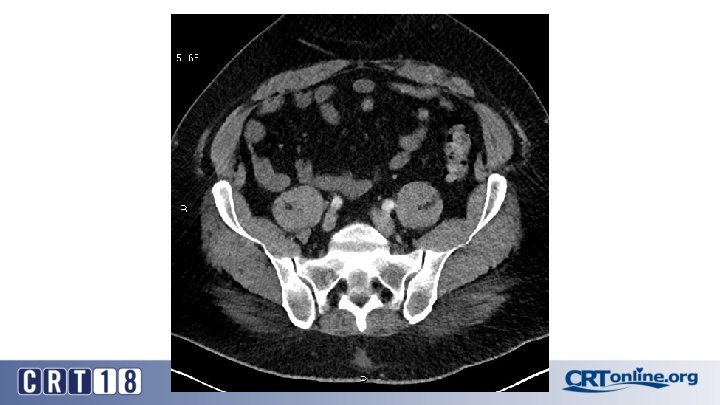

Blue Toe Syndrome

Returns Next day

Failed recanalization: BKA